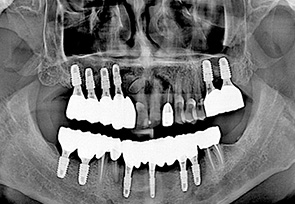

before

after